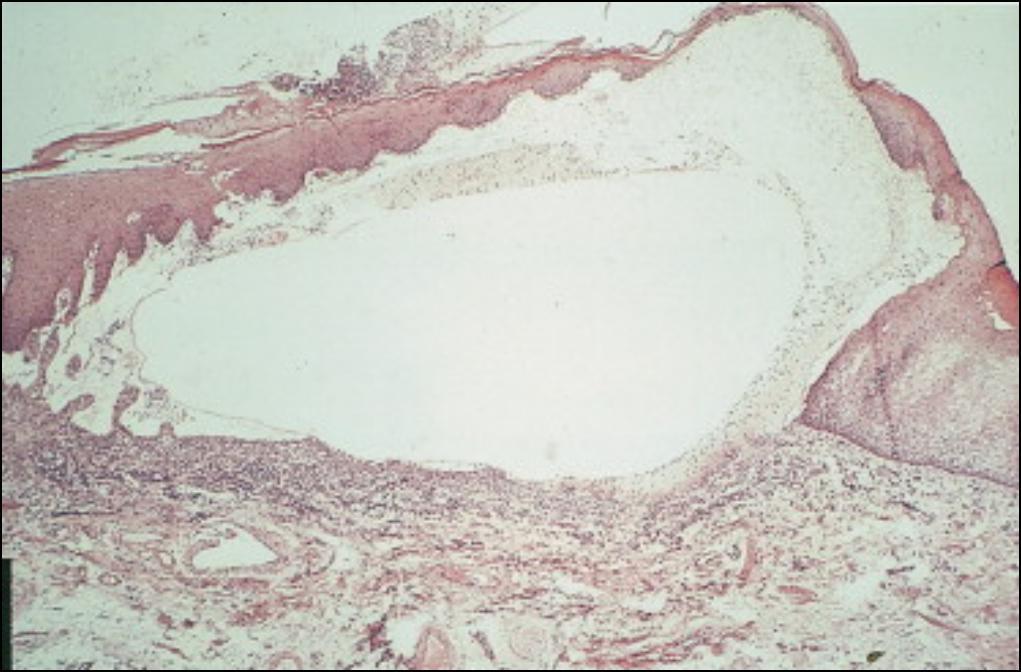

Voilà l’anapath d’une biopsie de bulle cutanée. Pas de médicament récent. Qu’est ce que c’est?

Bulle sous-épidermique, pas d’acantholyse, pas de nécrose kératinocytaire = c’est une pemphigoide bulleuse